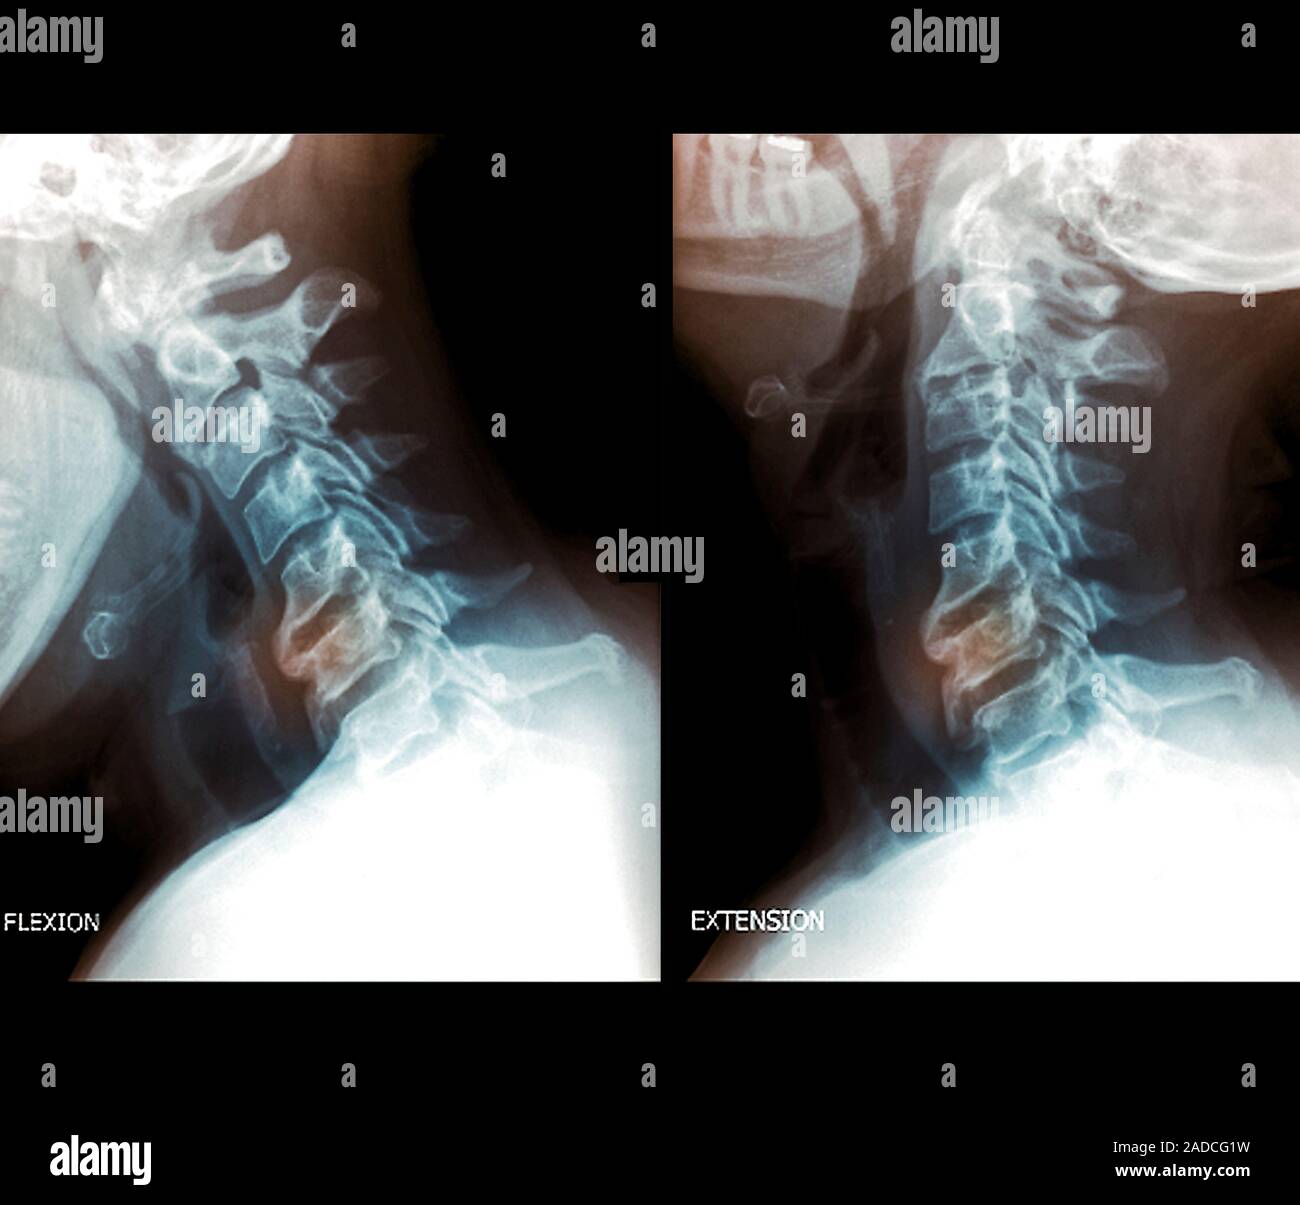

From www.alamy.com

Osteoarthritis of the cervical spine. Coloured lateral Xrays of the Cervical Flexion And Extension X Rays the cervical spine flexion and extension views demonstrate the seven vertebrae of the cervical spine when the patient is in a. this online presentation reviews a variety of cervical spine entities, with case examples and illustrations to clarify concepts, and discusses differential considerations and potential diagnostic pitfalls. the cervical spine series is a set of radiographs taken. Cervical Flexion And Extension X Rays.